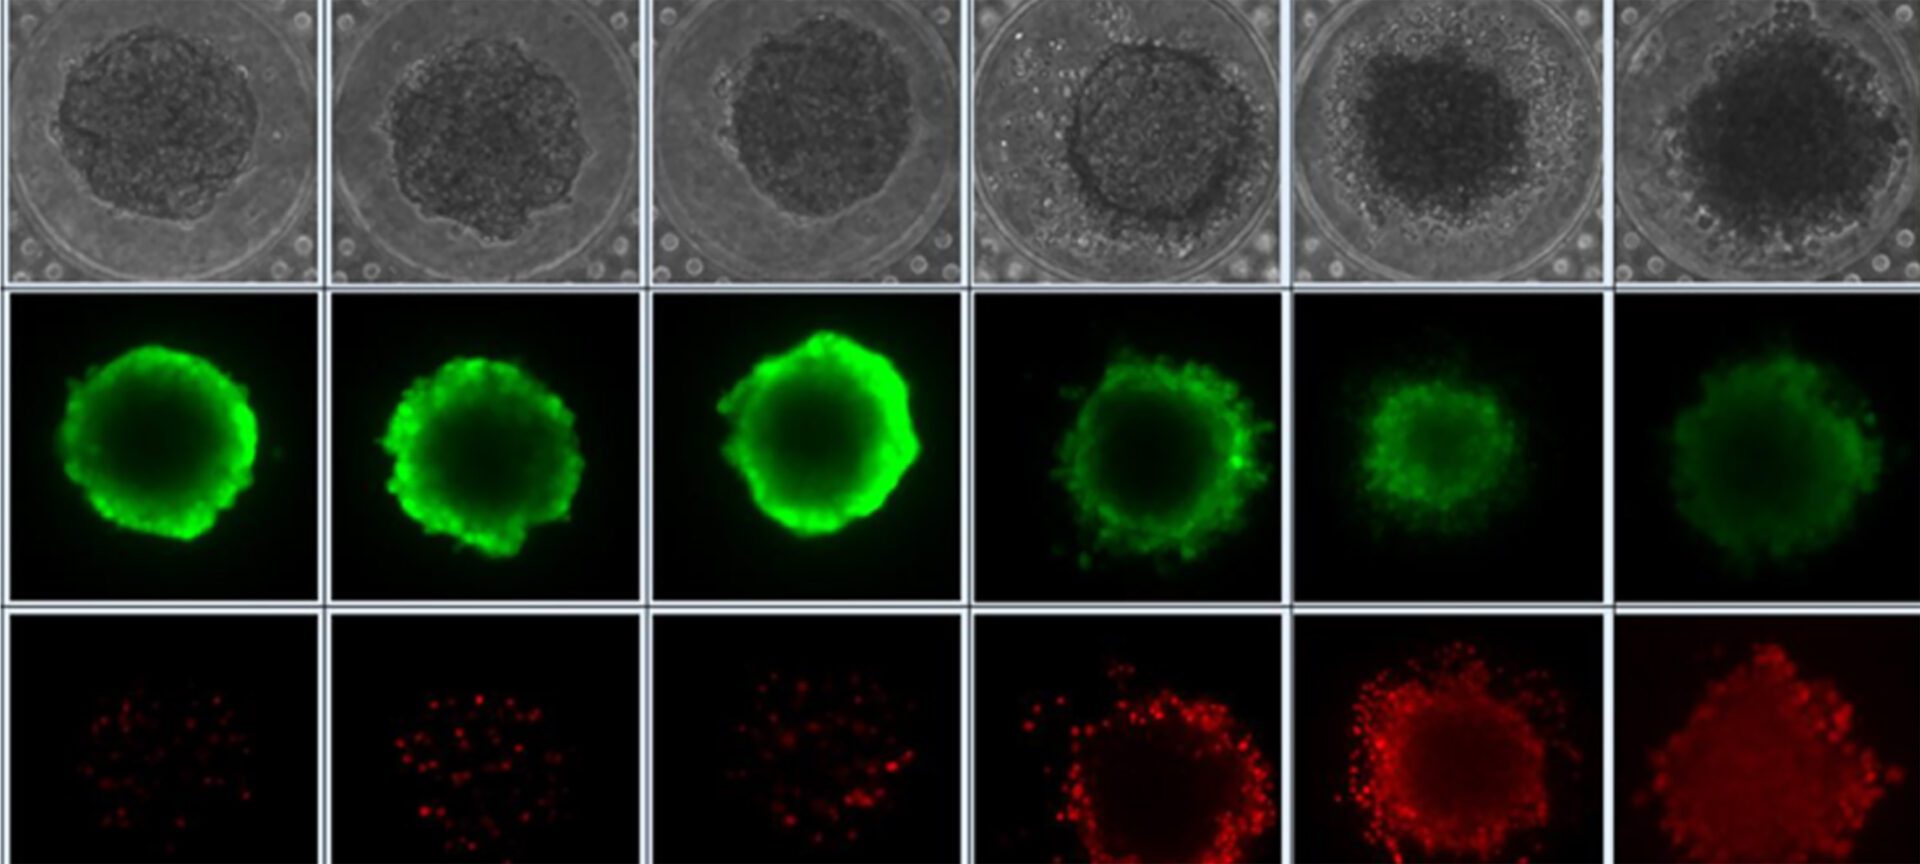

How sound waves trigger immune responses to cancer in mice

Technique pioneered at the University of Michigan could improve outcomes for cancer and neurological conditions.

Tumors partially destroyed with sound don’t come back, in rats

Technique pioneered at the University of Michigan could improve outcomes for cancer and neurological conditions.

The post Tumors partially destroyed with sound don’t come back, in rats appeared first on Michigan Engineering News.